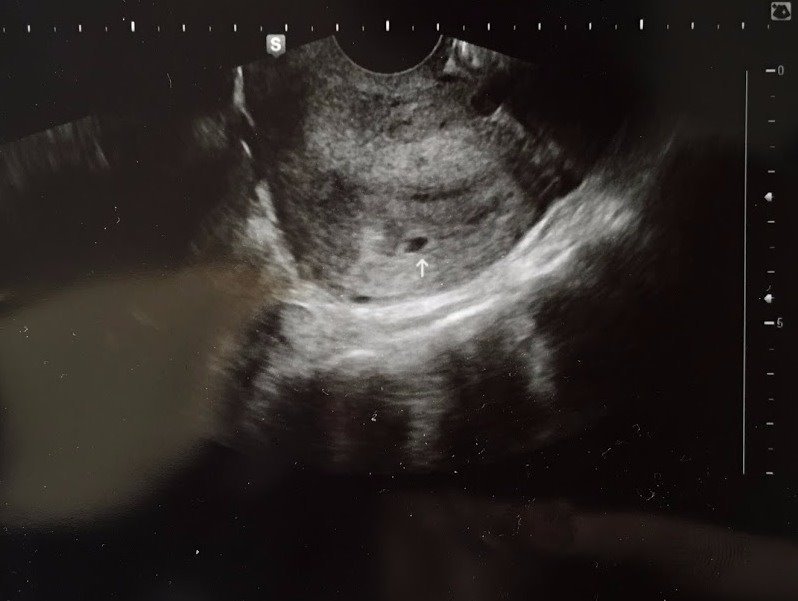

그리고 그날 첫 초음파 사진을 받았다.

첫 초음파 사진.

광활한 우주에 혹성 같은 검은 점이 아기집이고, 그 속에 ‘너’가 자라고 있다니, 정말 놀라웠다.